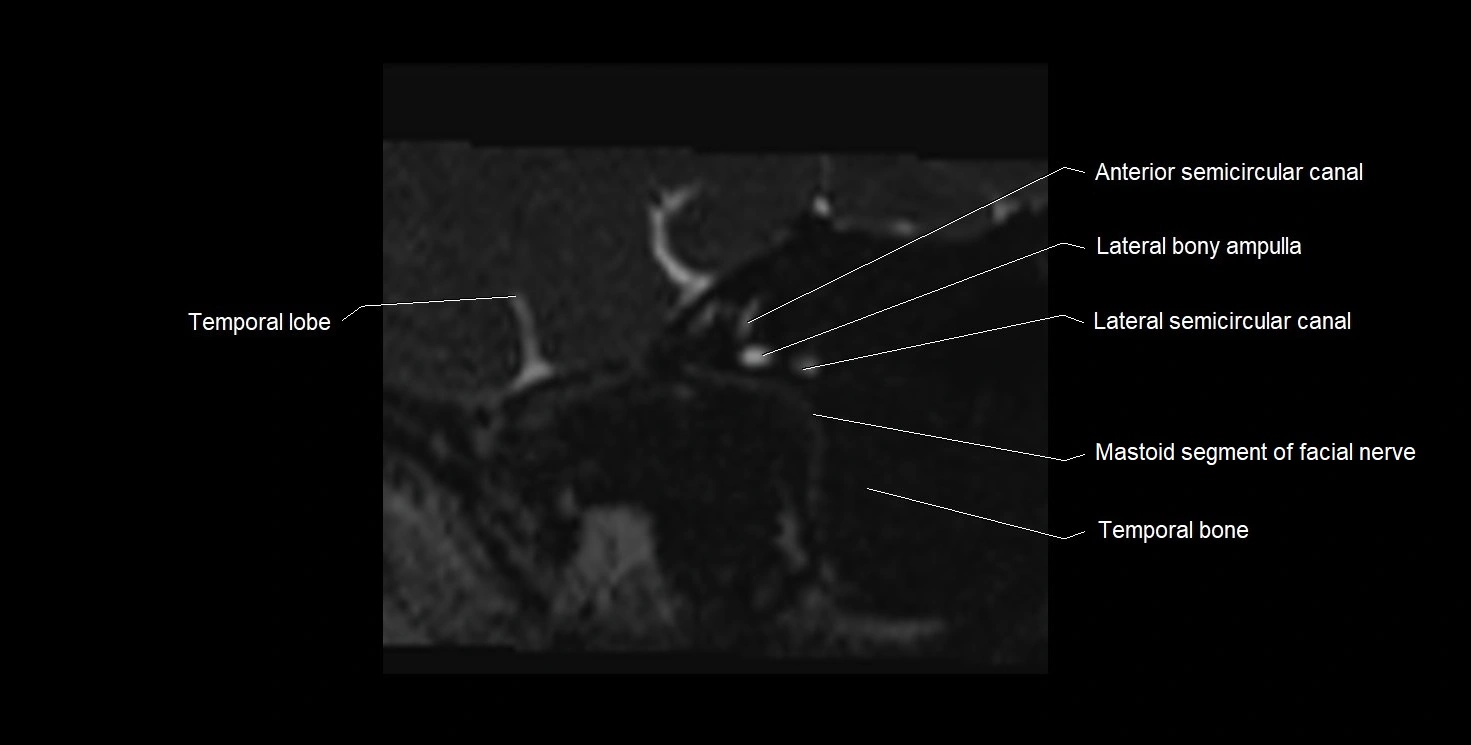

MRI images

image